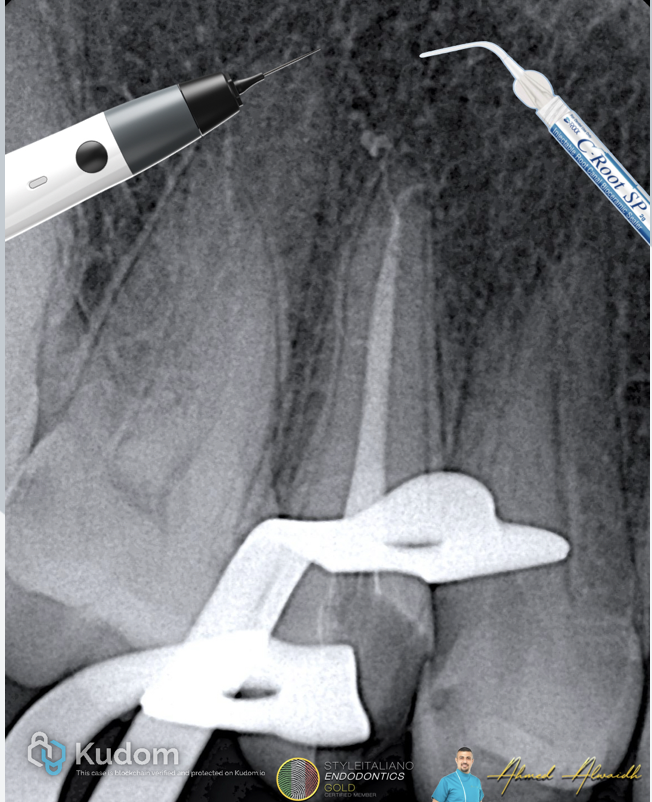

Fig. 1

IOPA showed UR5 with deep decay, and single wide canal that suddenly becomes narrow at the apical third, suggesting a split, which needs to be confirmed clinically.

Fig. 2

After infiltration anaesthesia and rubber dam isolation, access to UR5 revealed hyper inflamed pulp tissue. Single canal been prepared to #25/06 with two POEs (portal of exits) that were negotiated and prepared. NaOCl 3%, EDTA 17%, PUI

To ensure maximum hermetic seal of the root canal system, I have used combination of premixed hydraulic BC cement (C Root Dental) and thermoplacticised gutta percha

Fig. 3

Post obturation IOPA showing 3D obturation of the root canal system filling the two POEs